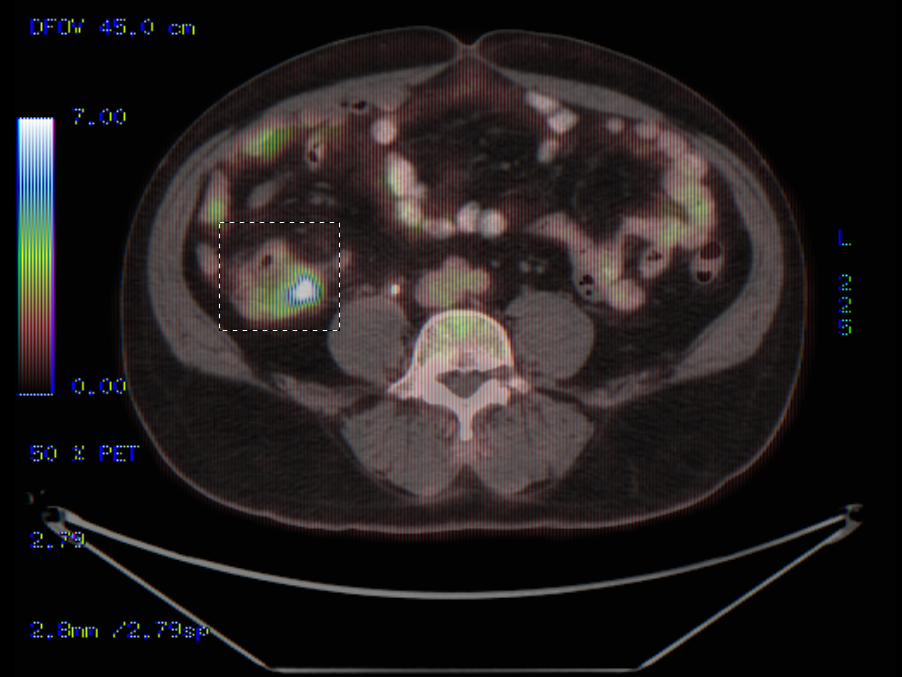

案例3

在右侧升结肠检测到局部病变

在右侧升结肠检测到局部病变